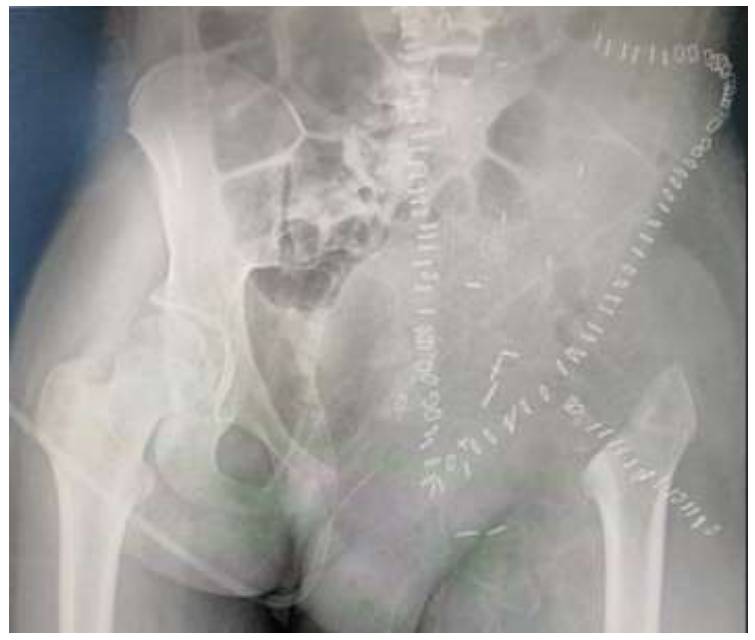

Post-surgery: It is visible on the X-ray after resection.